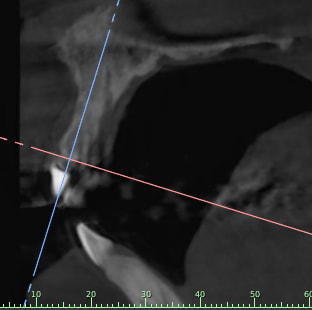

Je rajoutes quelques coupes et une rétro... C'est vraiment un massacre à la tronçonneuse!

24/04/2019 à 15h19

D'autres coupes et une rétro